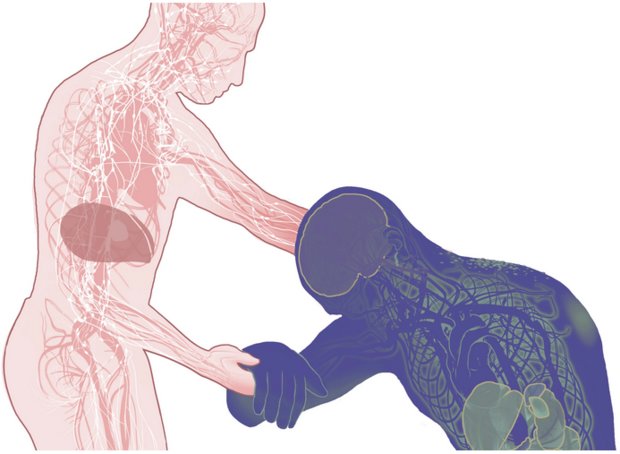

ویروس ابولا، قبل از اینکه از نابودی آبشاری سیستم ایمنی بدن، عروق خونی و اندام های حیاتی را آغاز کند، می تواند برای بیش از یک هفته در بدن پنهان بماند.

شروع

ذرات ویروس ابولا خون فرد آلوده و سایر مایعات بدن وی را اشغال می کند، این مایعات آلوده می توانند از طریق چشم ها، غشاهای مخاطی، خراشیدگی های روی پوست و یا از یک سوزن تزریق زیر جلدی وارد بدن شخص دیگری شود. اجساد افرادی که از این بیماری فوت کرده اند، بسیار خطرناک هستند. در روستاهای کوچک در غرب آفریقا، ارائه مراقبت شخصی نزدیک به بیمار یا اعضای خانواده فرد فوت شده به راحتی می تواند این بیماری را گسترش دهد.